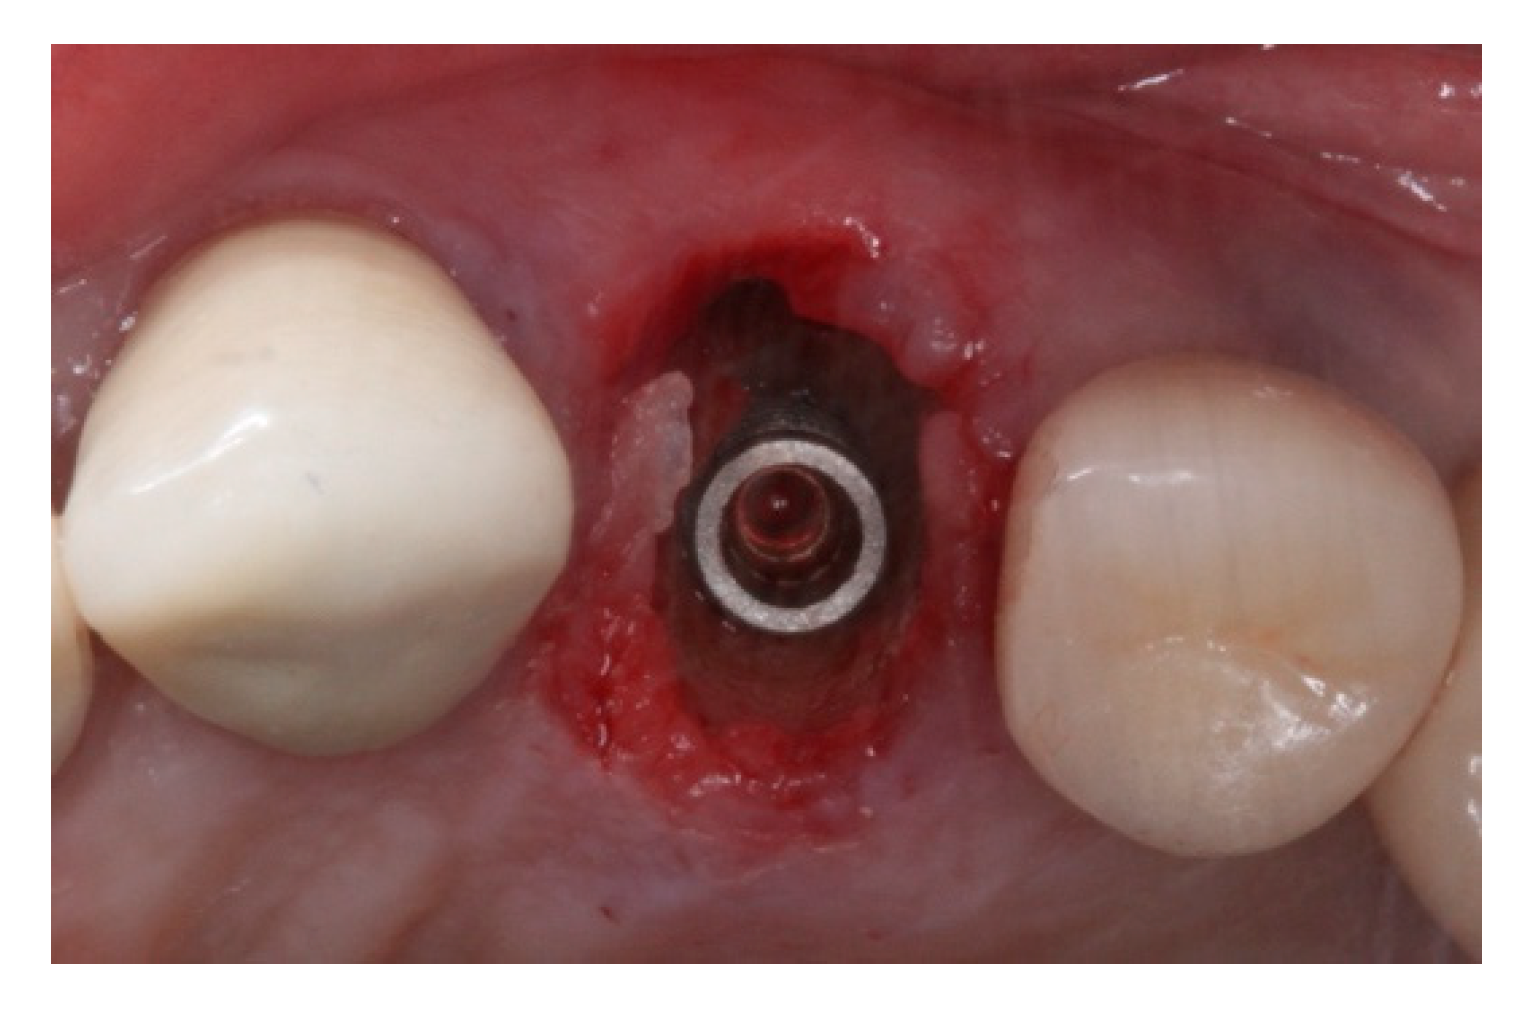

2. Materials and Methods